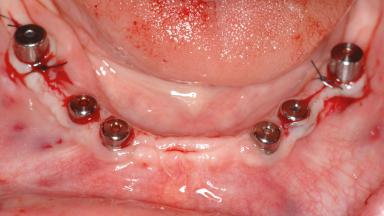

Le Fort I Interpositional Graft and Mandibular Sandwich Osteotomy for Maxillofacial Rehabilitation after Severe Periodontitis

A 47-year-old woman who had suffered from aggressive periodontitis requiring a number of periodontal interventions over more than 10 years was referred by her general dental practitioner and periodontologist for bone augmentation and implant therapy. Her failing dentition had already been scheduled for extraction. The patient expressed a desire for implant-supported fixed restorations and esthetic improvement of her lower face. She had agreed to consult with a maxillofacial surgeon after the referring dentist had suggested bone augmentation. An initial examination by the maxillofacial surgeon revealed mobility of all residual teeth in a patient who was very unhappy with the function of her removable partial dentures. Due to periodontally migrated flaring teeth and loss of occlusal support, the vertical dimension of occlusion was dramatically reduced. The patient was displeased with her lower face because of deepened nasolabial, commissural, and supramental folds.

# of Implants 14

Type of Implants Two-Piece

Bone Augmentation Horizontal|Sinus Floor Elevation|Staged|Vertical

Defining Characteristics Fully edentulous upper jaw to be rehabilitated with four or more implants

Modality Fixed hybrid bridge on 5+ implants